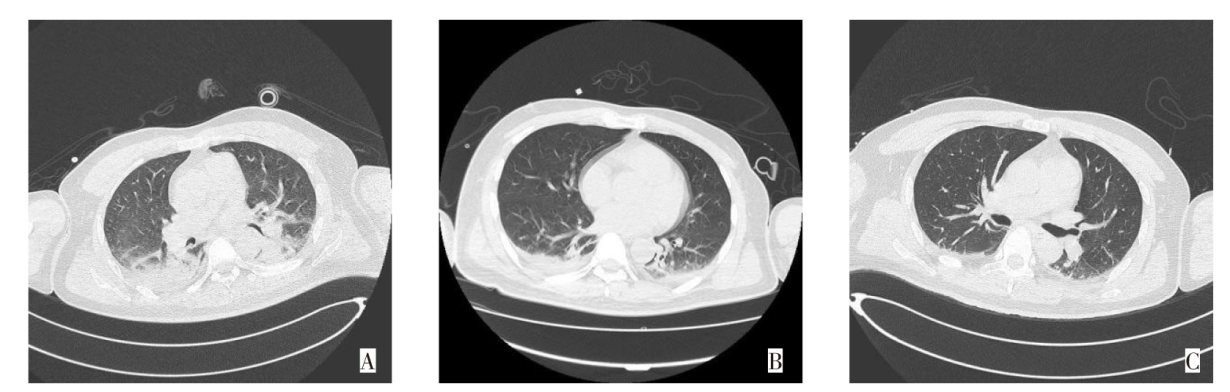

BAO C H, FENG Q, ZHANG C, et al. Heat stroke with significantly elevated troponin and dynamic ECG changes: myocardial infarction or myocardial injury?[J]. Am J Med Sci, 2024, 368(3):258-264. doi:10.1016/j.amjms.2024.06.005.